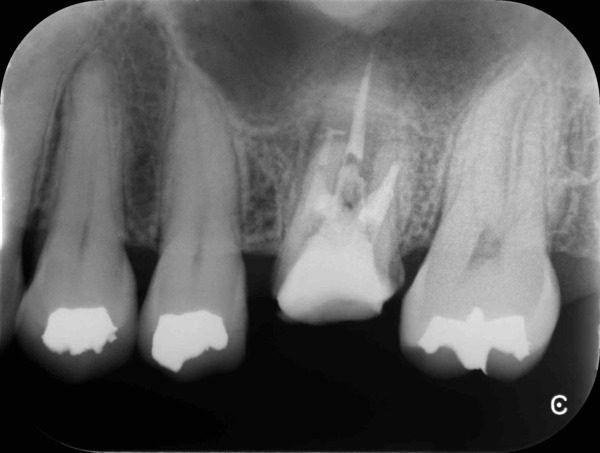

術前のレントゲン写真とお口の中の状態です。左上の前から6番目の歯(#26)です。

3本ある内の手前(近心)の根の中には治療用の器具が折れて残っていました。折れた器具が根管の中にあるだけでは問題になることは少ないですが、その先に感染がある場合は取り除いて治療をすることが望ましいです。

歯根の中の画像です。折れて残っている器具が確認できます。

超音波の器具を用いて取り除いていきます。今回は無事に取り除くことができました。

根の中を詰めた直後のレントゲン写真です。